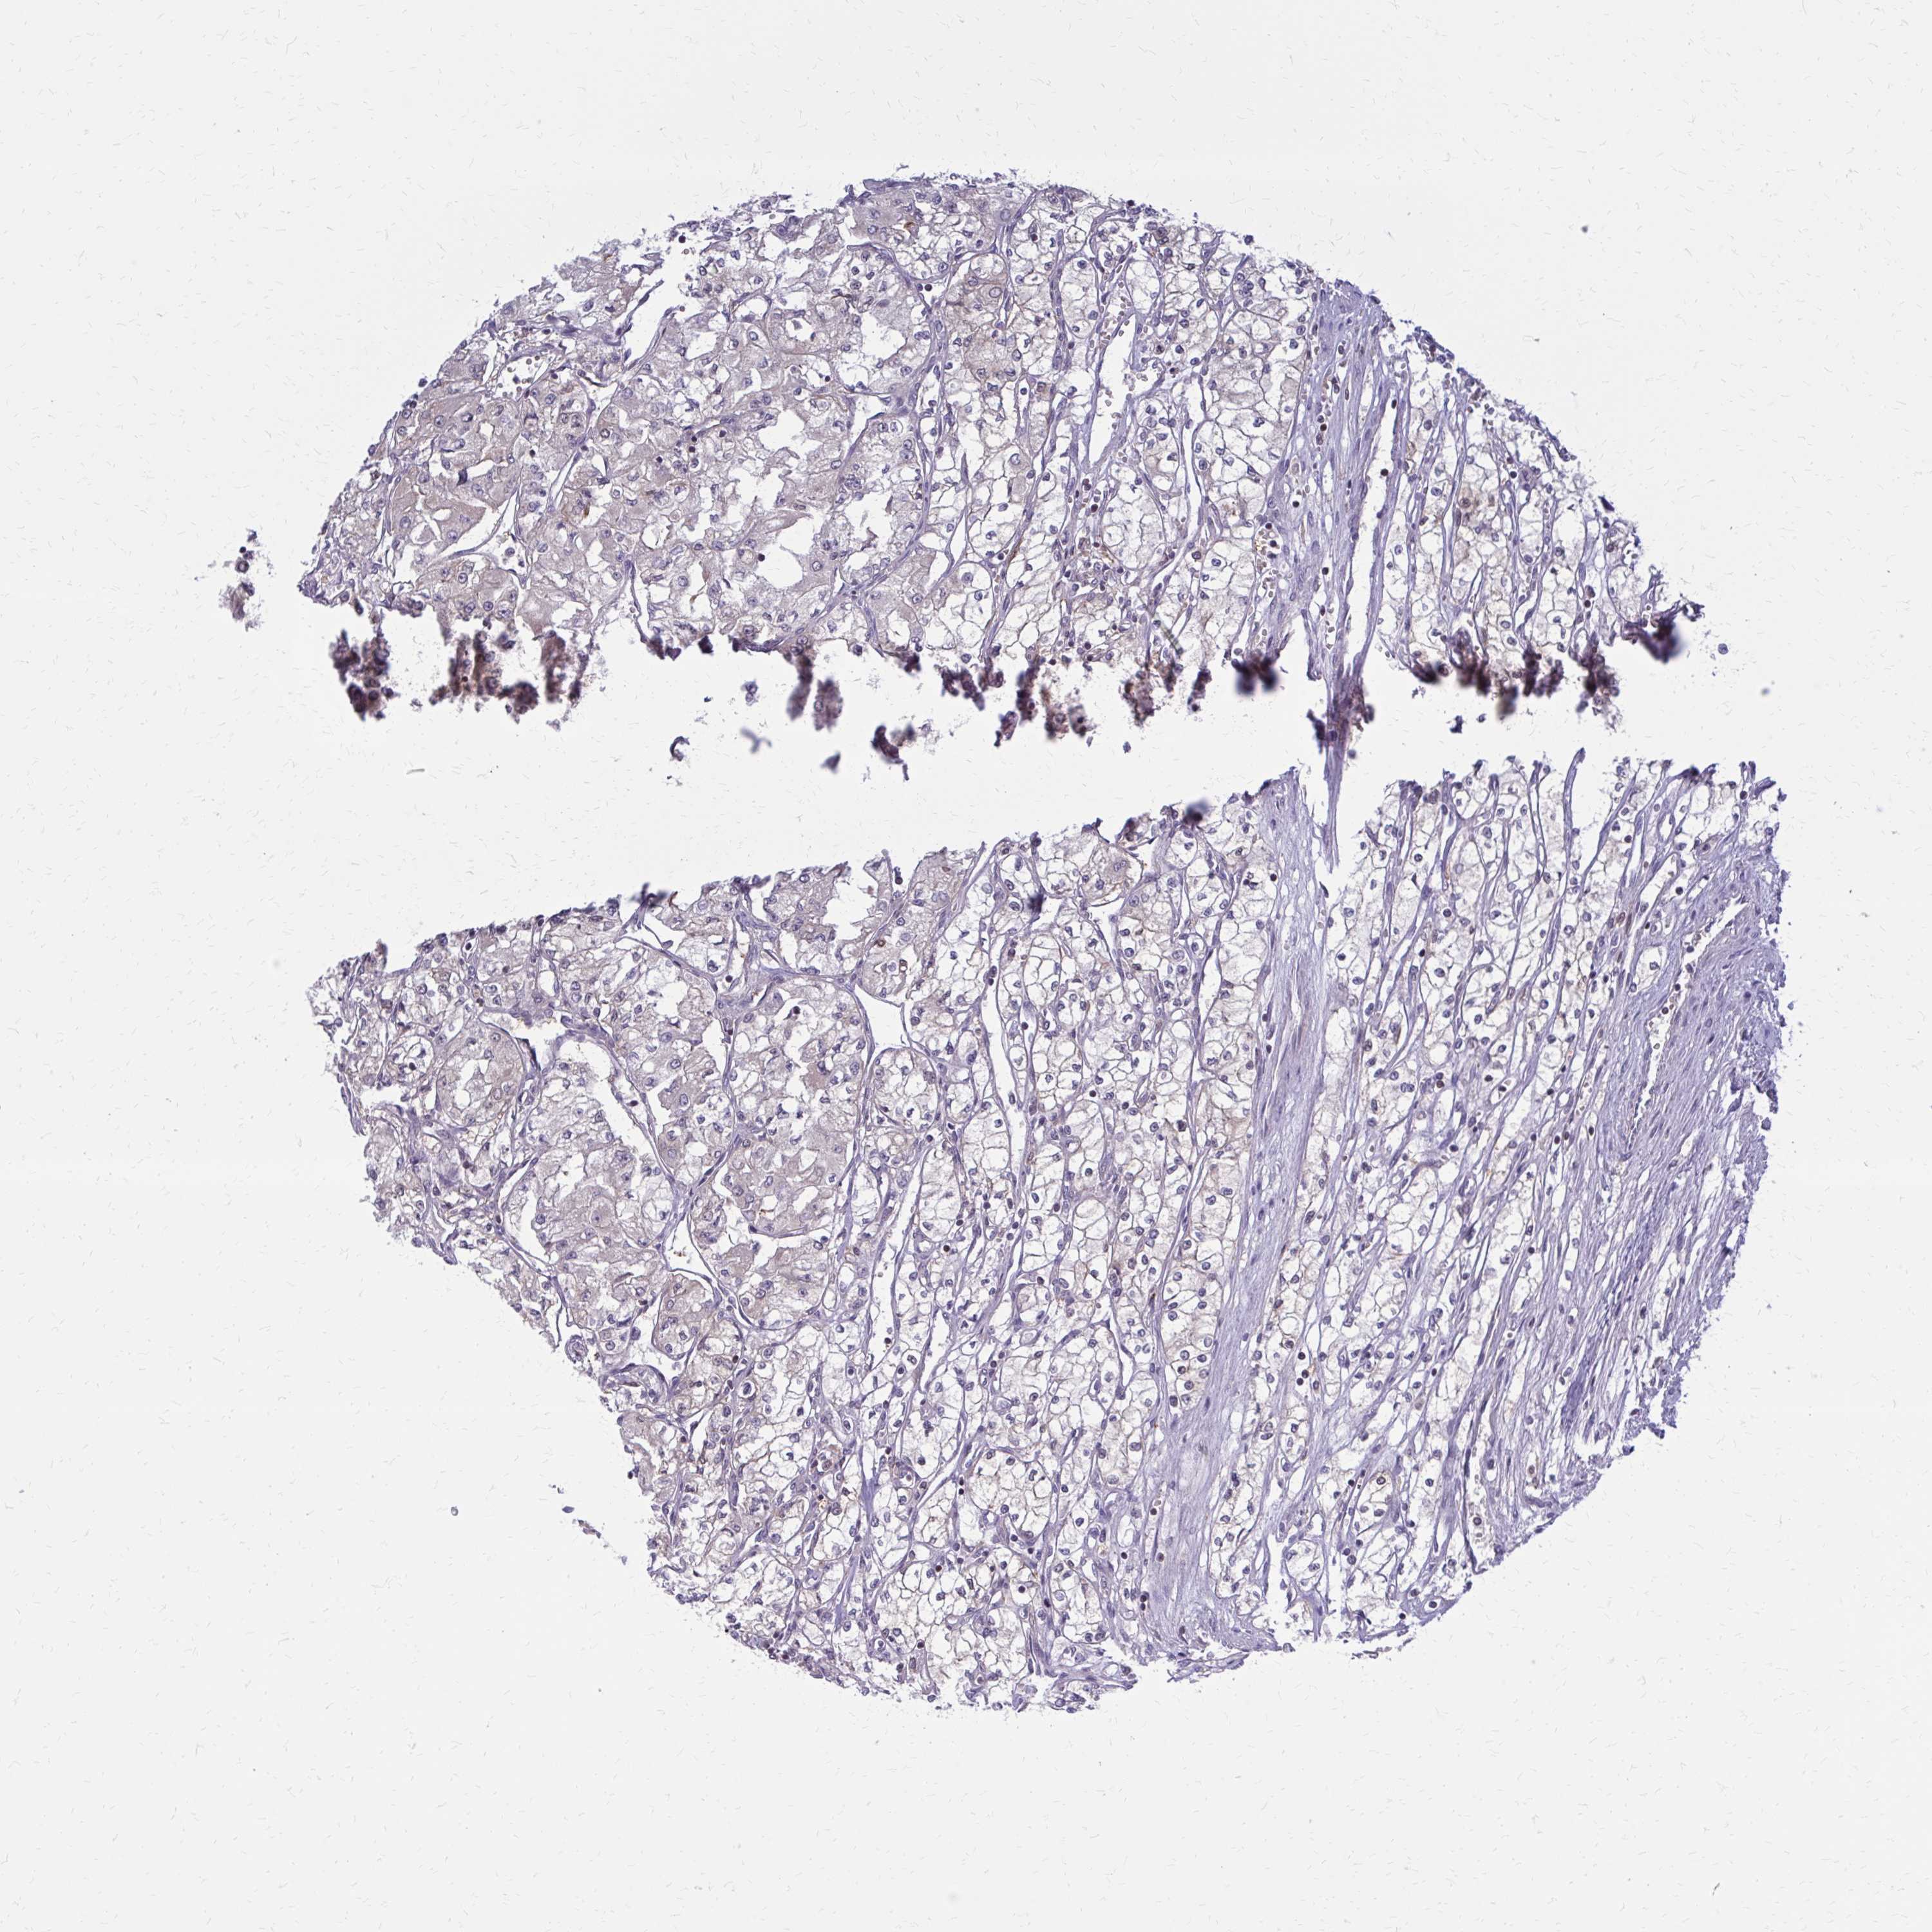

KIDNEY RENAL CLEAR CELL CARCINOMA (VALIDATION) - Interactive survival scatter ploti

The Survival Scatter plot shows the clinical status (i.e. dead or alive) for all individuals in the patient cohort, based on the same data that underlies the corresponding Kaplan-Meier plots. Patients that are alive at last time for follow-up are shown in blue and patients who have died during the study are shown in red.

The x-axis shows the expression levels (FPKM) of the investigated gene in the tumor tissue at the time of diagnosis. The y-axis shows the follow-up time after diagnosis (years). Both axes are complimented with kernel density curves demonstrating the data density over the axes. The top density plot shows the expression levels (FPKM) distribution among dead (red) and alive patients (blue). The right density plot shows the data density of the survived years of dead patients with high and low expression levels respectively, stratified using the cutoff indicated by the vertical dashed line through the Survival Scatter plot. This cutoff is automatically defined based on the FPKM cutoff that minimizes the p-score. The cutoff can be changed by dragging the vertical line or by entering a cutoff value in the square labeled "Current cut-off".

Under the Survival Scatter plot the p-score landscape (black curve; left axis) is shown together with dead median separation (red curve; right axis). Dead median separation is the difference in median mRNA expression between patients who have died with high and low expression, respectively. It is calculated as follows: median FPKM expression of dead patients with high expression - median FPKM expression of dead patients with low expression. This is intended to aid the user in visually exploring custom cutoffs and the associated p-scores and dead median separation.

Individual patient data is displayed and can be filtered by clicking on one or more of the category buttons on the top of the page. Categories describing expression level and patient information include: high, low, alive, dead, female, male and tumor stages. The scale of the x-axis can be toggled between linear and log-scale by clicking on the "x log" button. Mouse-over function shows TCGA ID, patient information and mRNA expression (FPKM) for each patient.

& Survival analysisi

Kaplan-Meier plots summarize results from analysis of correlation between mRNA expression level and patient survival. Patients were divided based on level of expression into one of the two groups "low" (under cut off) or "high" (over cut off). X-axis shows time for survival (years) and y-axis shows the probability of survival, where 1.0 corresponds to 100 percent.

DBI is not prognostic in Kidney Renal Clear Cell Carcinoma (validation)

Best expression cut offi

Based on the FPKM value of each gene, patients were classified into two groups and association between prognosis (survival) and gene expression (FPKM) was examined. The best expression cut-off refers the FPKM value that yields maximal difference with regard to survival between the two groups at the lowest log-rank P-value. Best expression cut-off was selected based on survival analysis .

When clicking on this number, the vertical dashed line indicating cut-off, the interactive survival plot, and the Kaplan-Meier curve will be adjusted to show results based on the best expression cut-off.

: 312.06

TCGA RNA samplesi

RNA-seq data is reported as average FPKM (number Fragments Per Kilobase of exon per Million reads), generated by the The Cancer Genome Atlas (TCGA) .

Normal distribution across the dataset is visualized with box plots, shown as median and 25th and 75th percentiles. Points are displayed as outliers if they are above or below 1.5 times the interquartile range. FPKM values of the individual samples are presented next to the box plot.

Average pTPM 273.5

Number of samples 100